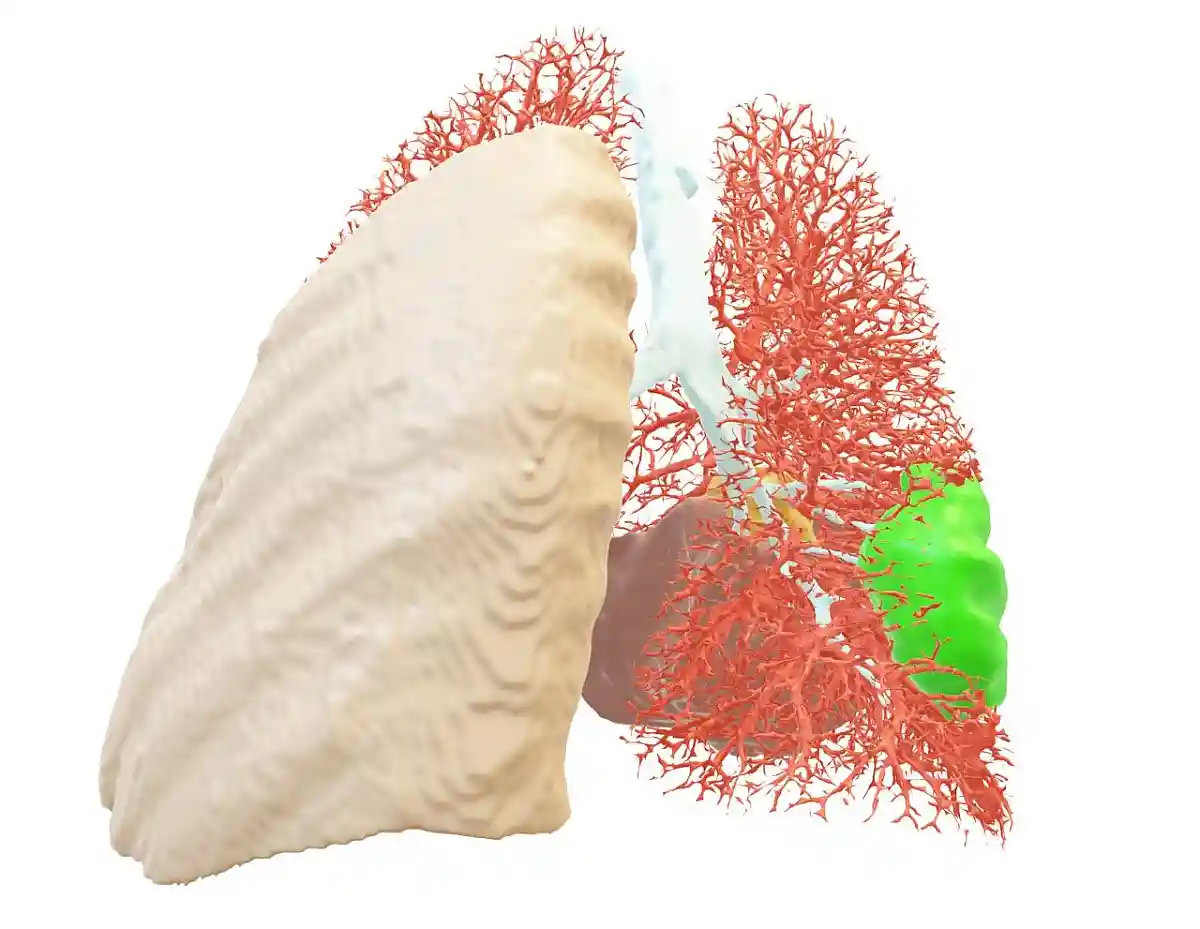

Зазвичай лікар -лікар призначає напрямок на КТ, ПЕТ або МРТ. Пацієнт приходить до рентгенівської шафи і фотографує. Ці скани вивчаються “Blumind AI”. Він здатний дати опис за три хвилини, що набагато швидше, ніж людина. AI може заощадити до 200 годин на одному дослідженні, кажуть розробники Bluemind AI. Більше того, це може створити 3D -візуалізацію внутрішніх органів людини і чітко показати, наприклад, пухлину.

Крім того, Роман Фіцджален з командою розробників вирішив навчити його ШІ шукати патології не лише серця чи печінки, але відразу максимальної кількості органів. ЩоBlumind ai“Навчається розрізняти 27 патологій.

Одне з головних завдань AI на початковій стадії – збільшення бази даних. “Blumind AI” спочатку довелося навчити розрізняти органи та виявляти захворювання. Робота кропітка. AI навчався на тисячах фотографій. І врешті -решт, точність діагнозу була донесена до 98,8%. Лікарі про цей результат мали лише мріяти. Це великий прорив.